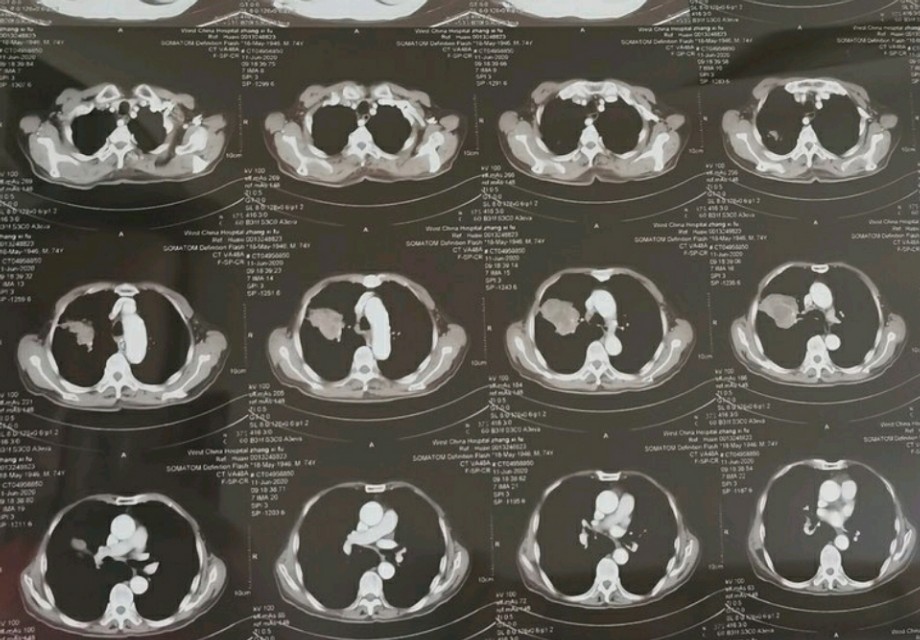

一位来自四川成都的肺癌患者家属通过网上诊室咨询我关于治疗的问题,这是位七十四岁老先生,诊断为肺鳞癌有至少三个月了,也用中医治疗了三个月,最近复查的片子显示肿瘤比四月份又增大了一厘米,当地医生也提出了自己的治疗意见,但是否治疗的决心,家属一直决定不下来。

看到他发过来的资料,右上肺这个肿瘤确实不小了,虽然目前没有明显的症状,但发展下去,各种症状就会随之而来,若身体状态好,还是有正规治疗的意义的,但需要家里统一意见才行,不管选择什么方案,不管选择治疗或者不治疗,我想,大家都会理解。不知道各位朋友怎么样看待这件事?